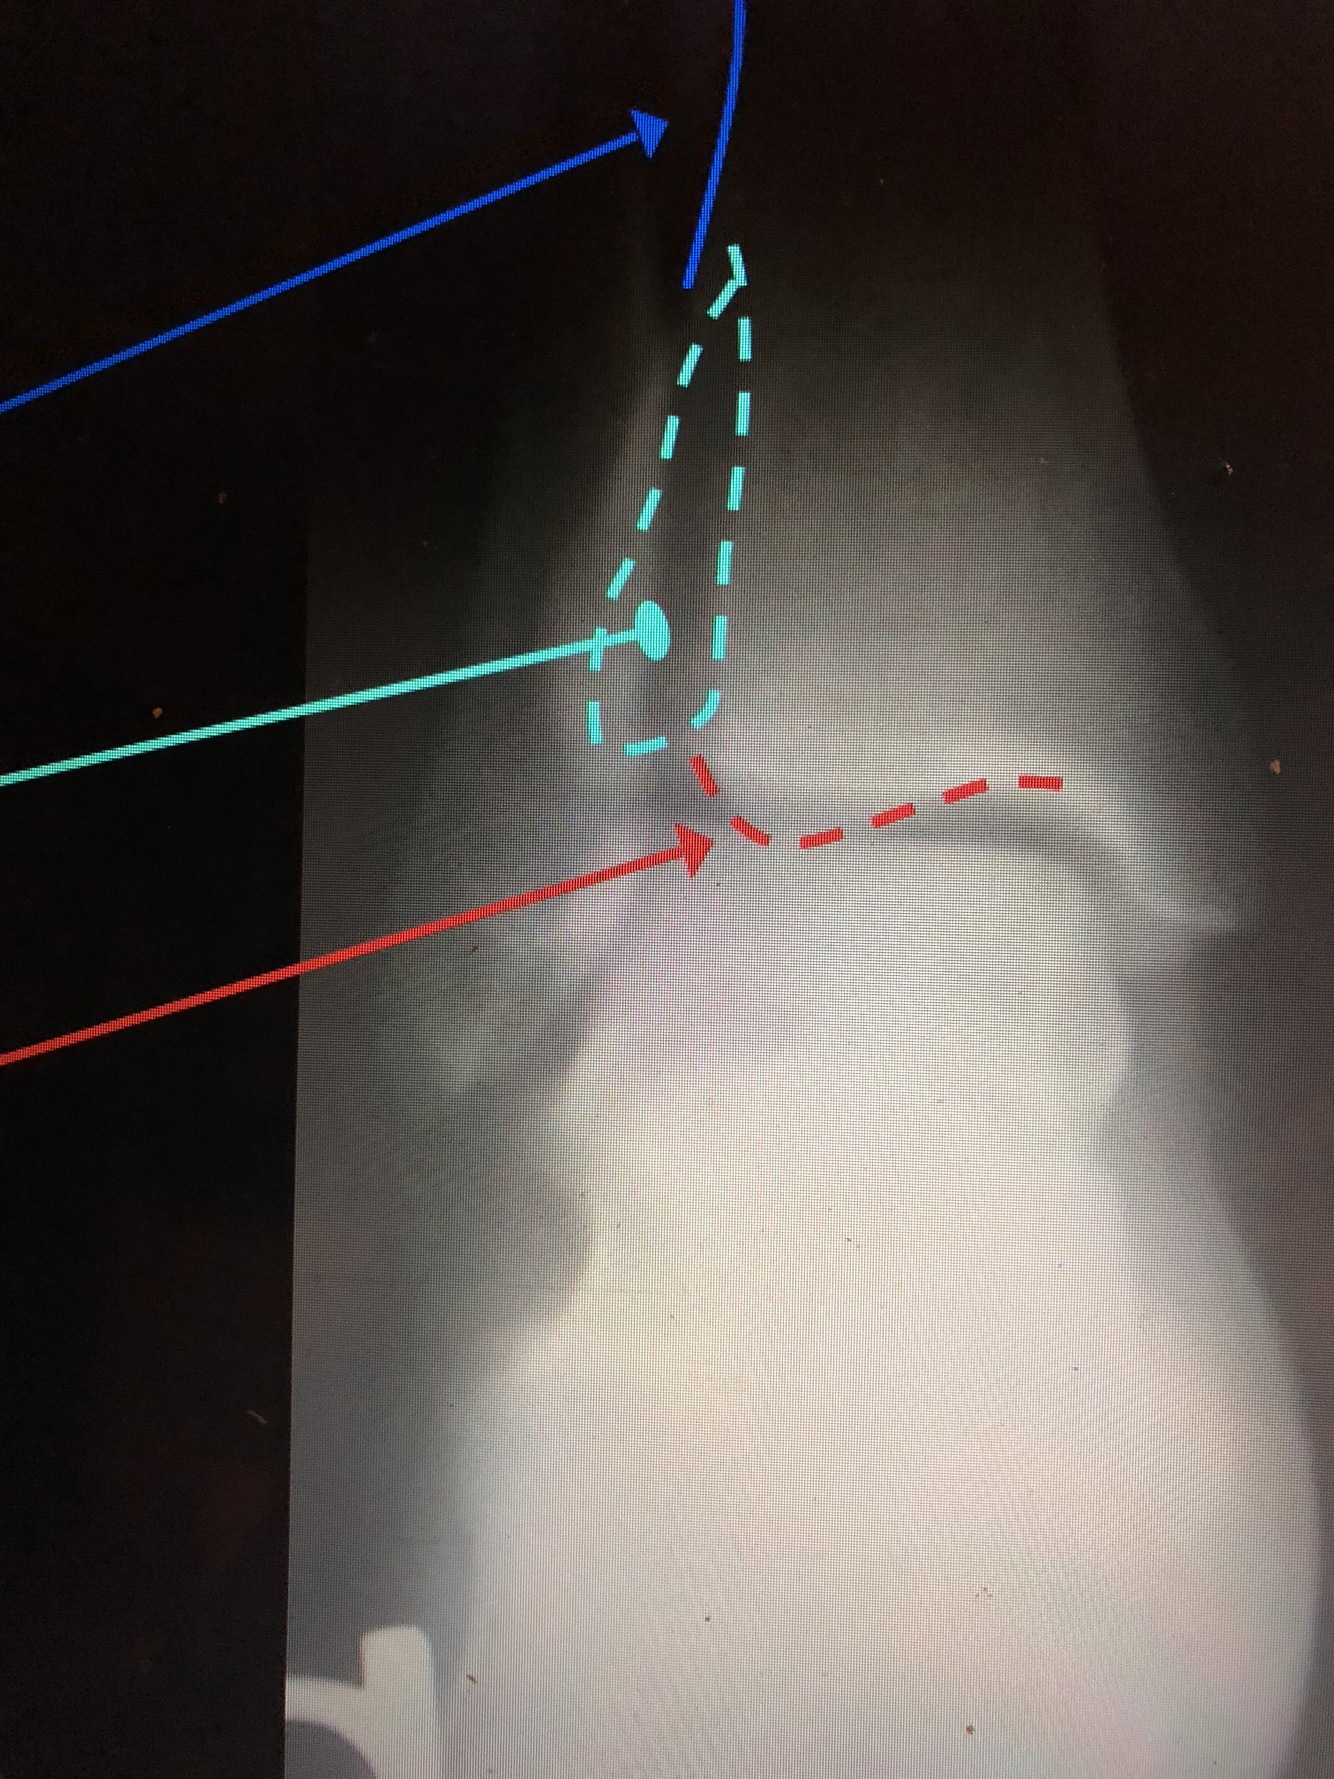

What is the dark blue line?

Interosseous Crest of the distal tibia

What is the light blue dotted line?

Fibular Notch

What is the red dotted line?

Posterior Malleolus